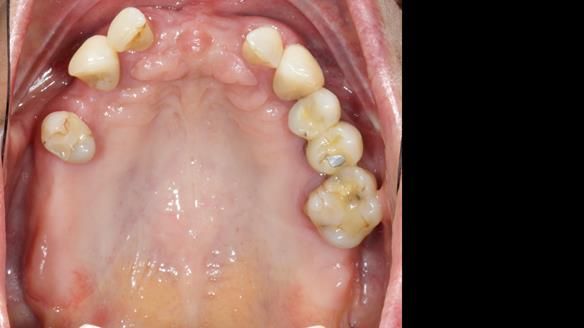

This is one of those cases that reminds me why I love removable prosthodontics. Pam was an absolute joy to treat — we were on the same page throughout. Her old upper flexible denture was loose, uncomfortable, and unaesthetic. We replaced it with a carefully designed metal-based upper partial denture/splint and new porcelain-bonded-to-zirconia (PBZ) crowns for the canines. The result is stable, comfortable, and natural-looking.

- Fit and reviews – fit of the denture/splint and new crowns, followed by reviews to fine-tune comfort and function. Ongoing support and one-year warranty.

The result

- Better support for lips and lower face.

- Natural smile and improved chewing.

- Designed to protect remaining teeth.

- Future additions possible if needed.